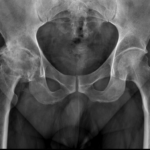

Arthritis is inflammation of the joints resulting in pain, swelling, stiffness and limited movement. Hip arthritis is a common cause of chronic hip pain and disability. The three most common types of arthritis that affect the hip are:

- Osteoarthritis: It is characterized by progressive wearing away of the cartilage of the joint. As the protective cartilage wears down, the bone ends rub against each other and cause pain in the hip. Rheumatoid arthritis: This is an autoimmune disease in which the tissue lining the joint (synovium) becomes inflamed, resulting in the production of excessive joint fluid (synovial fluid). This leads to loss of cartilage causing pain and stiffness.

- Traumatic arthritis: This is a type of arthritis resulting from a hip injury or fracture. Such injuries can damage the cartilage and cause hip pain and stiffness over a period of time.

The most common symptom of hip arthritis is joint pain and stiffness resulting in limited range of motion. Vigorous activity can increase the pain and stiffness which may cause limping while walking.

Diagnosis is made by evaluating medical history, physical examination and X-rays.